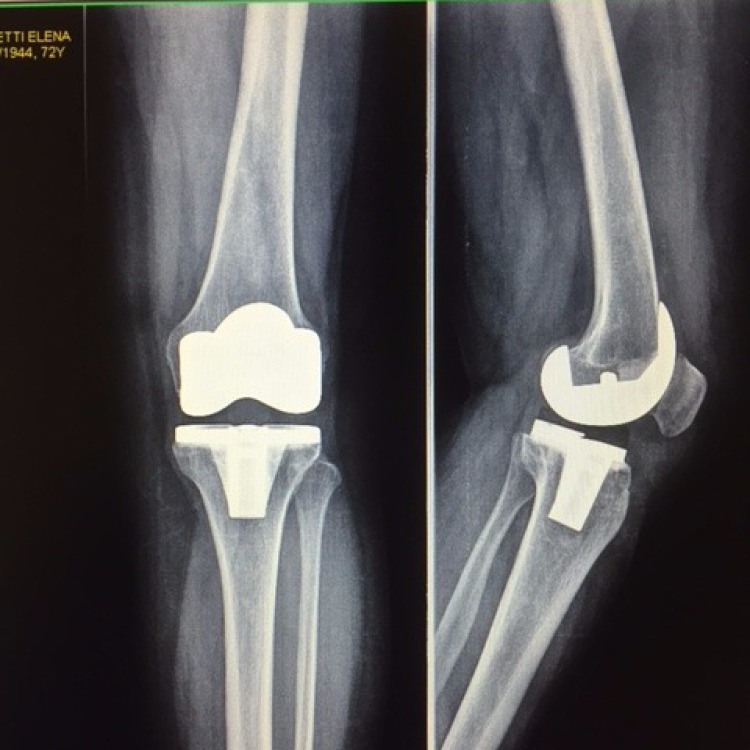

1-L'impianto deve essere eseguito bene: è l'elemento più scontato, ma fondamentale. Una protesi ben impiantata ci permette di avere tutti i requisiti fondamentali per poter durare nel tempo e dare soddisfazione al paziente.